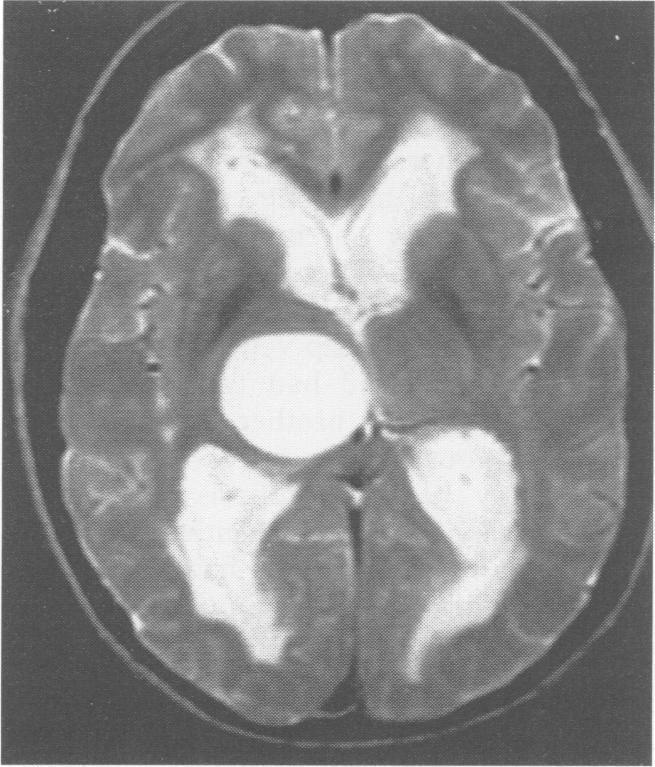

Obstructive hydrocephalus due to benign cysts of the thalamus: report of two patients.

J Neurol Neurosurg Psychiatry. 1996 Aug;61(2):203. doi: 10.1136/jnnp.61.2.203.

Obstructive hydrocephalus due to benign cysts of the thalamus: report of two patients.丘脑良性囊肿导致的梗阻性脑积水:两例患者报告。